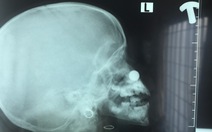

Mũi cậu bé 14 tuổi bị hủy vì u sợi mạch vòm mũi họng dài 12cm

TTO - Bệnh nhi 14 tuổi bị u sợi mạch vòm mũi họng khá lớn với chiều dài khoảng 12cm. Chúng hủy toàn bộ đáy xoang bướm và xâm lấn vào xoang bướm, hố chân bướm khẩu cái bên phải của bệnh nhi.